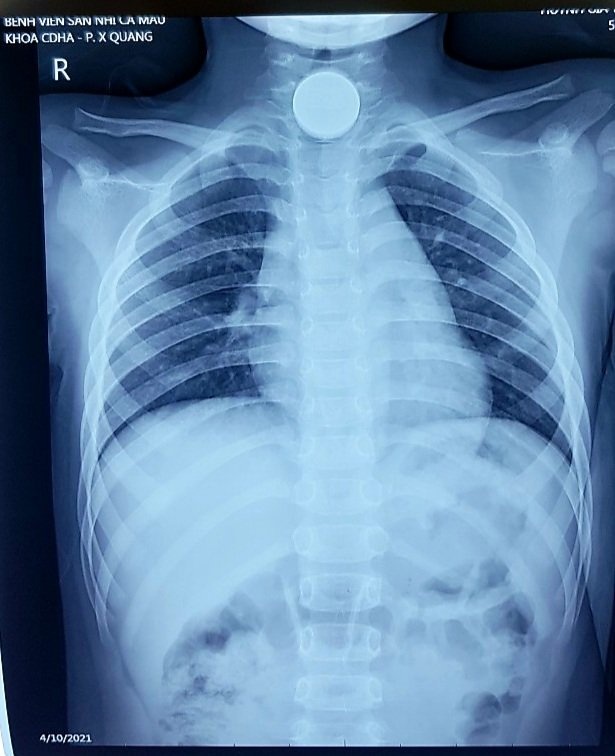

Bé được đưa tới cấp cứu tại một phòng khám tư nhân trước khi chuyển tới Bệnh viện Sản - Nhi Cà Mau. Hình chụp X-quang cho thấy đồng xu mắc kẹt ở thực quản đoạn cổ - ngực.

Hình ảnh chụp X-quang của bệnh nhi mắc đồng xu ở thực quản. Ảnh: BVCC.